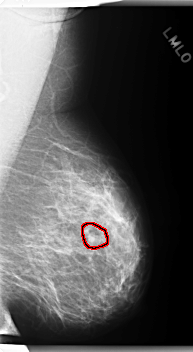

C_0277_1.LEFT_MLO

LEFT_MLO LINES 5976 PIXELS_PER_LINE 3272 BITS_PER_PIXEL 12 RESOLUTION 50 OVERLAY

FILE: C_0277_1.LEFT_MLO.OVERLAY

TOTAL_ABNORMALITIES 1

ABNORMALITY 1

LESION_TYPE MASS SHAPE LOBULATED MARGINS CIRCUMSCRIBED

ASSESSMENT 3

SUBTLETY 4

PATHOLOGY BENIGN

TOTAL_OUTLINES 1

BOUNDARY